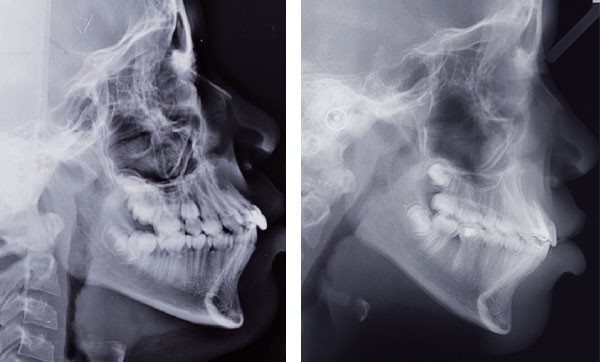

Situation clinique (fig. 1 à 9)

À l’examen clinique, Orlhane présente une classe I biproalvéolie aggravée par 11 fracturée et 25 enclavée et une classe II canine légère gauche. Cette malocclusion est associée à une classe II squelettique par promaxillie sur un schéma facial hyperdivergent. Il est décidé de ne pas traiter la biproalvéolie et la classe II squelettique modérées d’origine ethnique chez cette patiente.